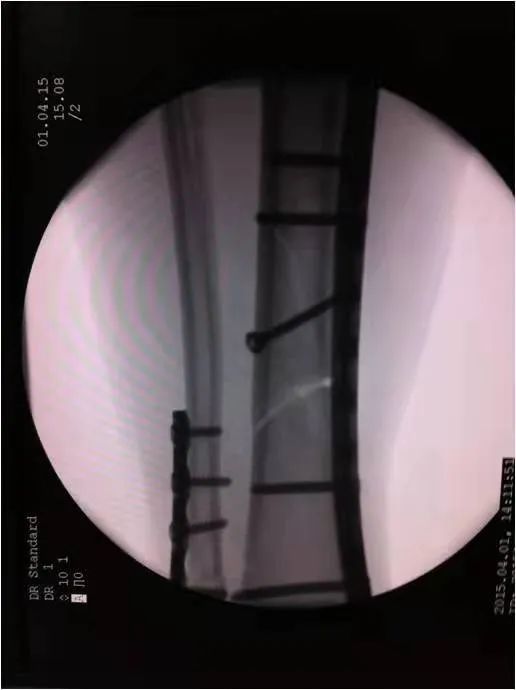

如采用傳統(tǒng)手術需大范圍剝離軟組織,手術切口在18公分,損傷面大,影響骨折愈合。經過科內術前討論后與患者及家屬溝通后,呂國福主任決定行小切口微創(chuàng)鈦板植入內固定手術治療,術中植入內固定物并剝離軟組織,此方法對周圍皮膚破壞小,手術切口最小僅0.5公分,極大降低皮膚壞死及后期出現骨不連發(fā)生幾率,從而達到解剖復位。

在急診科,檢驗科,麻醉科共同努力下,僅用一小時完成整個手術,術中出血量少、過程順利,手術非常成功。術后,呂國福主任數次查房,仔細查看患者的傷口愈合情況,關心患者的心理狀態(tài),為患者樹立信心,鼓勵患者進行功能鍛煉。